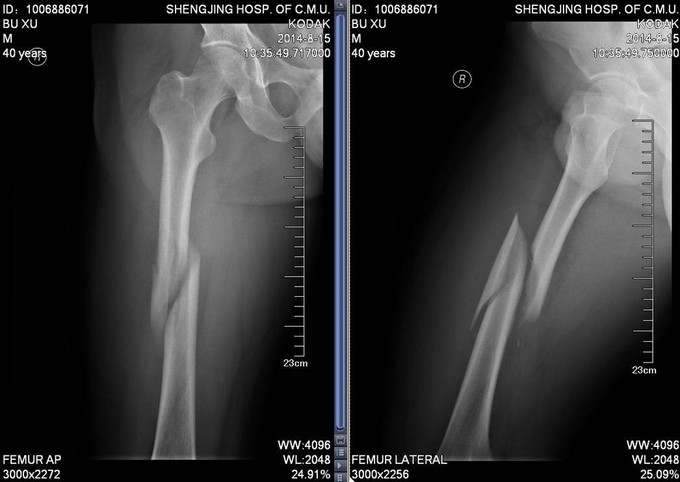

患者于2014-8-14 13:30左右,工作时不慎被重物砸伤,当时无法站立,自觉头晕,意识清楚,自觉大腿部疼痛,无法活动,被急送往我院急诊,经检查诊断为“右股骨干骨折”,给予对症处置,并请我科会诊,现患者为进一步诊治,转入我科病房,我科以“右股骨干骨折”为诊断收入院,患者伤后无昏迷,无恶心呕吐,无呼吸困难,至今未排便排气

右大腿肿胀,活动受限,压痛(+),骨擦音(+),骨擦感(+),可见异常活动,患肢皮肤感觉较健侧未见明显异常;足趾活动灵活,肌力正常,末梢循环可,足背动脉可触及。

诊断:右股骨干骨折 患者入院后急诊行右胫骨结节骨骼牵引术,术后维持患者长度,减轻患者疼痛,完善相关检查后,行右股骨干骨折闭合复位髓内针内固定术。